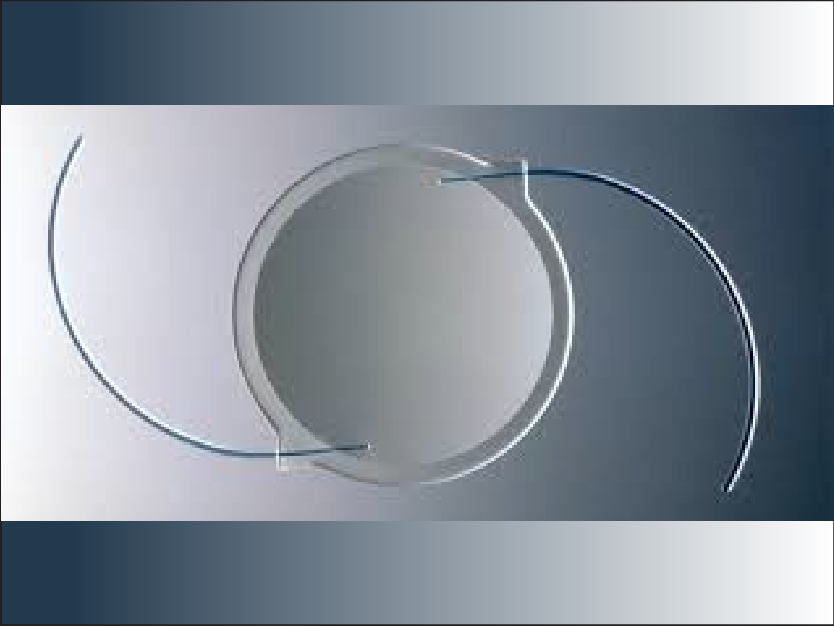

Cataract Surgery

Cataracts are the most common reason for vision loss in the U.S., and Parker Cornea provides specialized procedures to combat the disease, including Toric lenses and EDOF / Multifocal lenses.

Lens Exchange

If an artificial lens is creating a problem after cataracts surgery, Parker Corneal specialists can provide help, including removing and replacing the lens with a better performing model.